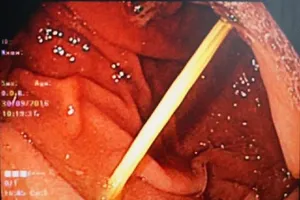

Ăn bánh canh nuốt luôn tăm tre mà không biết

09/10/2016 10:59